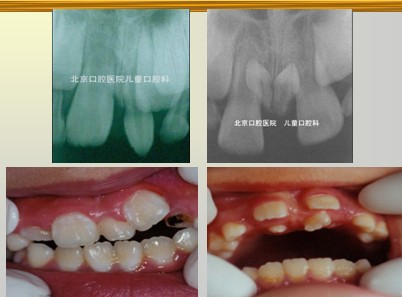

牙齿发育时期受到障碍(遗传、环境、全身、局部)而引起牙齿的数目、形态和组织结构改变,超出了正常范围者称为牙齿发育异常。 数目异常包括:额外牙、缺额牙(先天缺牙)、个别牙缺失或部分牙缺失、无牙症。额外牙的病因不明确,牙源性上皮活性亢进;牙板上皮过度增殖;发育缺陷(颅骨锁骨发育不全、腭裂);遗传、家族性。额外牙 Supernumerary teeth的临床表现:发生率1-3%,乳牙列少见。好发部位:上前牙区(98.3%),最常见上中切牙之间。形态:锥形,,不规则形、与正常牙相似。性别差异:男性多于女性。萌出,或阻生于颌骨内。

解析: 额外牙

额外牙对牙列的影响:恒牙的发育和萌出、牙间隙、牙齿移位、邻牙扭转、邻牙牙根吸收与正常牙融合、恒牙迟萌或阻生 — 含牙囊肿和美观。I其治疗包括:早期发现,适时拔除,及时拔除萌出的多生牙;择期拔除阻生的多生牙,以不影响正常牙发育为原则;埋伏无病变的多生牙,需要定期观察;可替代正常牙的多生牙应予保留。